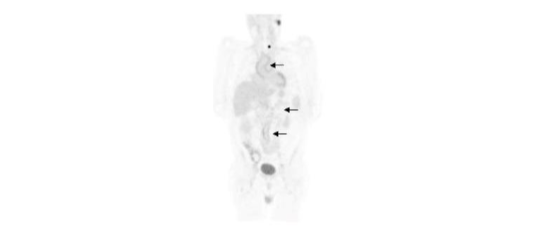

The workup of the patient with fever of unknown origin, or FUO, consists of first line investigations including history and physical examination, laboratory tests, chest x-ray, and echocardiography. When these investigations fail to yield a diagnosis, second-line tests including CT, MRI, and molecular imaging studies are performed. At one time the mainstays of molecular imaging for FUO, ⁶⁷Ga and WBC imaging have been replaced by ¹⁸F-FDG as the molecular imaging test of choice for this entity in both adults and children (Figure 19).

Figure 19.

Vasculitis. There is diffusely increased ¹⁸F-FDG activity throughout the aorta (arrows). Vasculitis is a well-recognized cause of fever of unknown origin in the elderly. ¹⁸F-FDG is very sensitive for detecting large-vessel vasculitis and has shown promise for monitoring treatment response.

A positive result contributes useful information by identifying the etiology of the fever and/or guiding further management, while a negative result excludes focal disease as the cause of the fever. A negative result also is a good predictor of a favorable prognosis. Performed early in the FUO workup, ¹⁸F-FDG PET/CT is cost effective by reducing the number of diagnostic procedures performed, obtaining a diagnosis sooner, and decreasing the number of undiagnosed cases⁷⁵. A recent consensus panel recommended that ¹⁸F-FDG PET/CT is an important diagnostic test after a patient fulfills FUO criteria with few or no diagnostic clues⁷⁶.